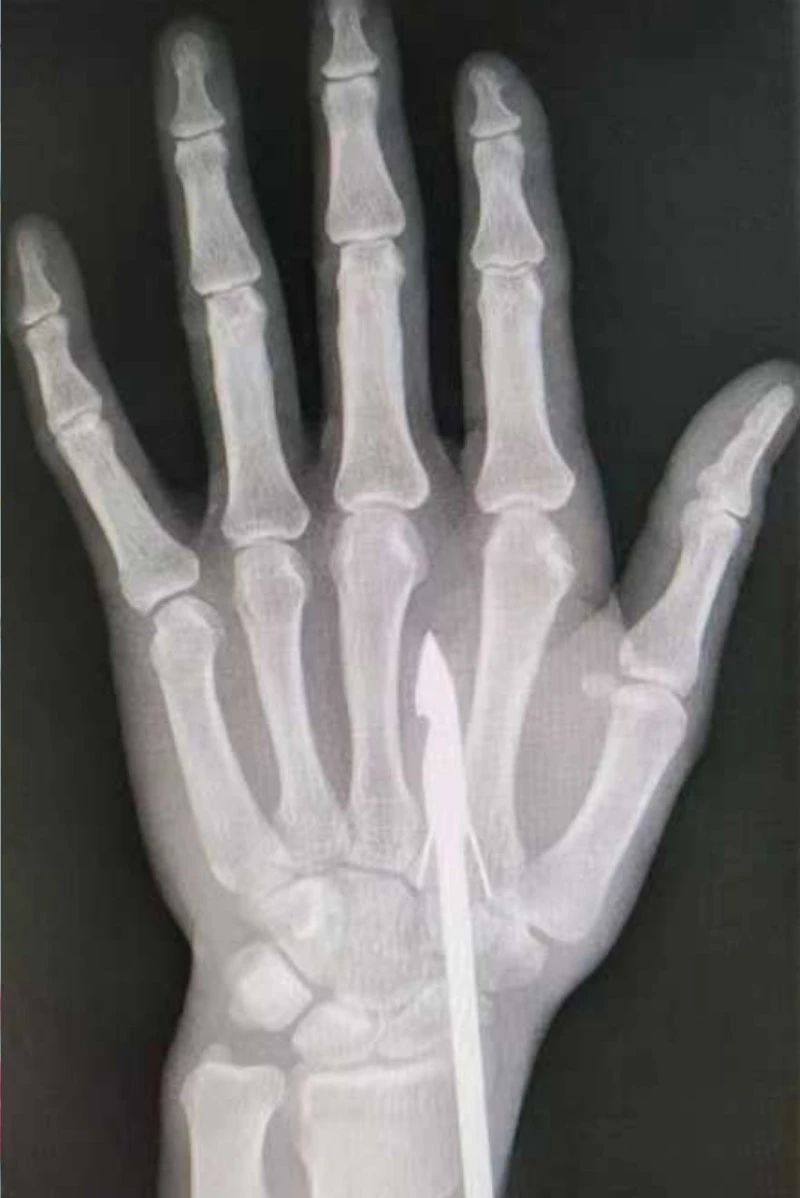

時間緊迫,每一秒的流逝都可能對傷者的手部功能造成不可逆的損害。接診醫(yī)生代彭威,迅速對傷者進行了初步檢查。他注意到,魚鉤已經(jīng)深深嵌入皮膚,情況遠比表面看起來復雜。沒有絲毫猶豫,立即安排了X線檢查以確認魚鉤的位置及傷及范圍,以及急診化驗檢查以評估患者的整體狀況。

確保在取出魚鉤的同時,不對周圍的組織造成額外的傷害。8點15分左右患者在局部浸潤麻下進行手術,經(jīng)探查后魚鉤未傷及重要血管、神經(jīng)及肌腱,經(jīng)過緊張的十分鐘,魚鉤終于被順利取出,隨后對傷口進行了仔細的清理和縫合,用敷料仔細包扎,確保傷口能夠順利愈合。